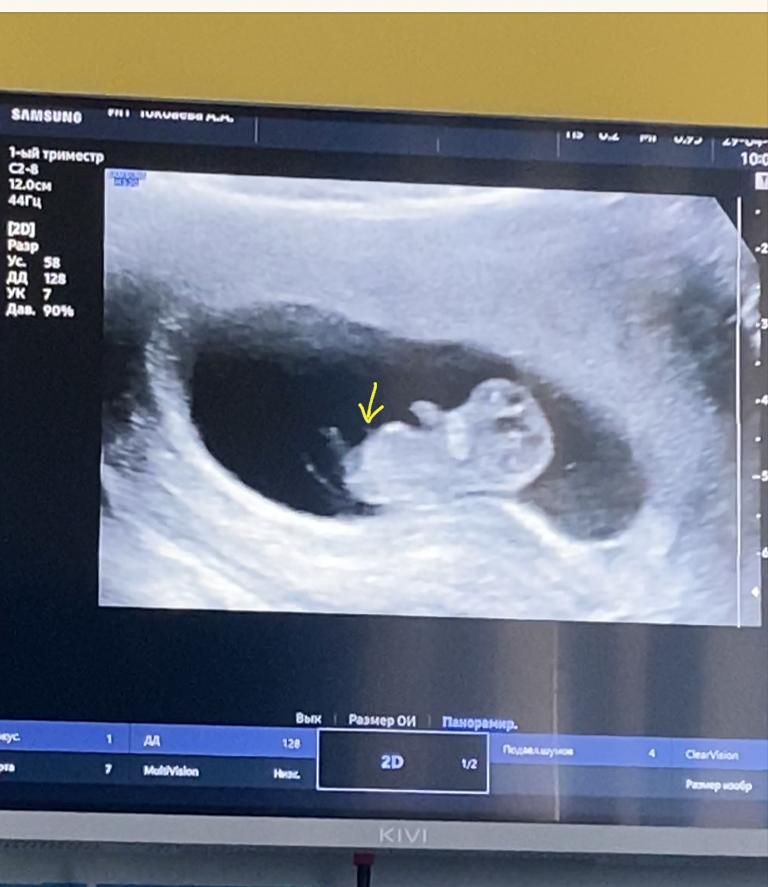

Узи 9-10 недель.

Ольга, Вот когда мне показывали снизу там что-то прям торчало,но возможно и пуповина так себя показала)

Я вообще пока сардельку вижу 😂мне кажется раньше 12 недель не стоит смотреть точно))) даже на бугорок

в 13 девочку самый крутой узист города поставил, а в 18 уже мальчиком стал. там не видно еще ничего, тем более того, что вы указываете на фото))))подождите еще чуть чуть